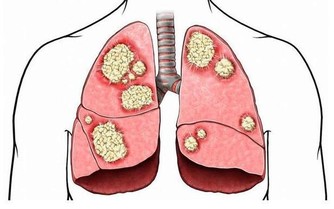

更為重要的是,越來越多的研究發現:有糖尿病的人常吃水果比從不吃水果,各種並發症發生的風險將下降20%,這不僅是因為水果起到了上述作用,水果中含有大量的維生素、微量元素、礦物質也更有利於營養均衡,確保機體各項代謝的正常進行。